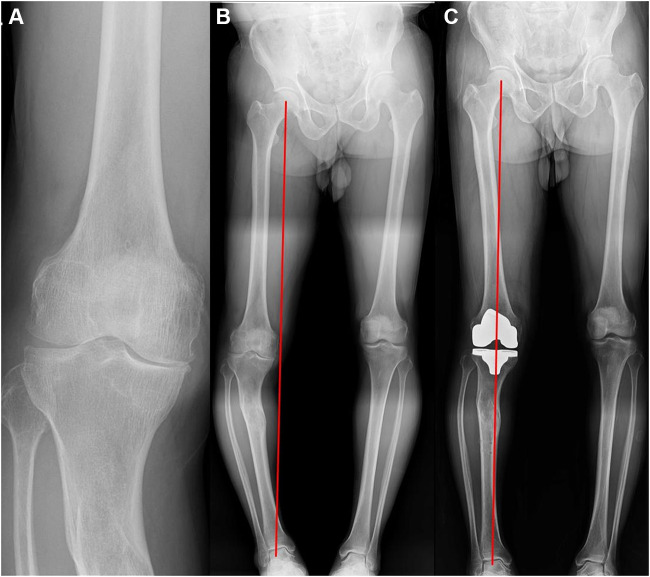

背景:在股骨或胫骨创伤后关节外畸形的情况下,实现适当的轴对齐可能是困难的。我们介绍了机器人辅助全膝关节置换术(TKA)对伴有创伤后关节外畸形的膝关节骨性关节炎患者的放射学结果。方法:我们分析了5例患者(1)Kellgren-Lawrence (K-L) III-IV级骨关节炎膝关节,(2)股骨或胫骨存在创伤后关节外畸形,(3)接受机器人辅助TKA的患者的5个膝关节的结局。对他们的放射学表现进行了评估。结果:所有初始畸形的5个膝关节(平均14.8°,范围12.7-18.5°)均被矫正为中立位(平均0.7°,范围-1.1-2.7°)。术后髋关节-膝关节-踝关节(HKA)角度无异常值。结论:我们的研究结果表明,机器人辅助的TKA可以用于创伤后关节外畸形患者实现正确的肢体对准。

Methods: We analyzed the outcomes of five knees in five patients with (1) Kellgren-Lawrence (K-L) Grade III-IV osteoarthritic knees, (2) the presence of posttraumatic extra-articular deformities either in the femur or the tibia, and (3) who underwent robot-assisted TKA. Their radiological findings were evaluated.

Results: All five knees with initial deformity (mean 14.8°, range 12.7-18.5°) were corrected to neutral alignment (mean 0.7°, range -1.1-2.7°). There was no postoperative outlier of hip-knee-ankle (HKA) angle.